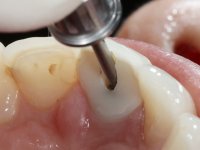

After the impression of the implant using a double-mix technique with double viscosity and the collection of shape and color information by the ceramist, we proceed with the work. In the model, a syn octa was placed over the implant, and a screw was placed on it to assess its emergence in relation to the incisal edge. Then, an adequate emergence profile in the artificial gingiva was prepared. A abutment with characteristics suitable for overbite and simultaneously capable of receiving a veneer was waxed on top of this scenario. This waxing gave rise to the manual milling of a very personalized abutment. An infrastructure in Zr was also made for the veneer with a very great adaptation to the abutment. On this infrastructure ceramics were placed. Ceramic fluorescence sought to compensate for the lack of fluorescence that Zr had and obviously further customize the aesthetics. The adhesive bridge was removed and the definitive work was placed. The syn octa was initially tightened with 35 N to the implant and then the Zr abutment was tightened over the syn octa with 15 N. The access hole was plugged and then the veneer was cemented with resin-reinforced glass ionomer. After 15 years, the patient returned to the consultation with tooth mobility. Fortunately, nowadays we have the possibility of having dynamic tightening wrenches that allow tightening screws with greater inclinations. An access cavity was made without damaging the incisal edge of the veneer. Tightening was done with a dynamic wrench with 15 N torque. The hole was covered with Teflon and filled with composite resin. This solution allowed the problem to be solved in a simple and economical way.